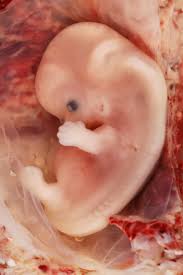

WHAT DOES IT TELL ABOUT MY BABY SO EARLY?

- It tells you the exact duration of pregnancy.

- It rules out pregnancy lying outside the uterus at early stage to safeguard your life.

- It tells you whether it is single or multiple pregnancies (Twins / Triplets).

- If you have observed any spotting or bleeding.